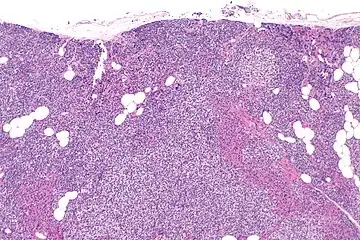

Parathyroid hyperplasia low mag.

Parathyroid hyperplasia medium mag.

Parathyroid hyperplasia high mag.

Primary hyperplasia of the parathyroid gland, results from both hypocalcaemia and increased phosphate levels by decreasing expression of calcium sensing receptors and vitamin D receptors at the parathyroid gland.[8][4] These decreases in receptor expression lead to hyperfunctioning of the parathyroid. Hyperfunction of the parathyroid gland is thought to exacerbate primary hyperplasia which evolves further to a secondary more aggressive hyperplasia. Histologically, these hyperplasic glands can be either diffuse or nodular.[24] Primary hyperplasia, usually resulting in diffuse polyclonal growth is manly related to reversible secondary hyperparathyroidism. Secondary hyperplasia of the parathyroid gland is more often a nodular, monoclonal growth that sustains secondary hyperparathyroidism and is the catalyst in the progression to tertiary hyperparathyroidism. Nodular hyperplastic glands in tertiary hyperparathyroidism are distinctly larger in both absolute size and weight up to 20-40-fold increases have been reported.[25][26][24]

Parathyroid glands are normally composed of chief cells, adipocytes and scattered oxyphil cells.[27][14] Chief cells are thought to be responsible for the production, storage and secretion of parathyroid hormone. These cells appear light and dark with a prominent Golgi body and endoplasmic reticulum. In electron micrographs, secretory vesicles can be seen in and around the Golgi and at the cell membrane. These cells also contain prominent cytoplasmic adipose.[27][14] Upon onset of hyperplasia these cells are described as having a nodular pattern with enlargement of protein synthesis machinery such as the endoplasmic reticulum and Golgi. Increased secretory vesicles are seen and decreased intercellular fat is characteristic.[27][24] Oxyphil cells also appear hyperplasic however, these cells are much less prominent.